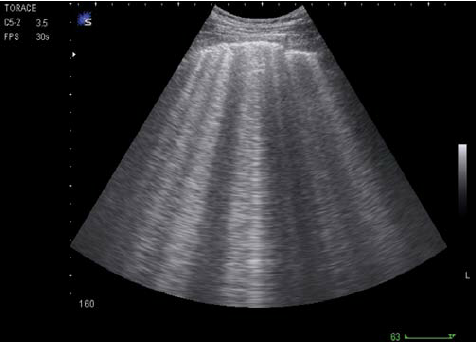

Can b line

Can b line 85 фотографий